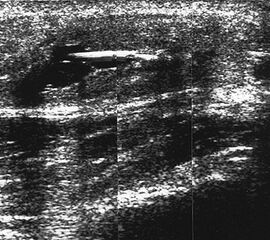

Ganglien imponieren als runde, echofreie Raumforderungen.

Abbildung 9

Lagerung: Rückenlage.

Schnittebene: LS und TS über der Pathologie.

Referenzstrukturen: Reproduzierbare knöcherne Landmarken in Abhängigkeit von der Lokalisation. Befunde: Ganglien finden sich häufig im fibularen Anteil der Gelenkkapsel des oberen Sprunggelenks (Abb. 9), aber auch an den Gelenkspalten und paratendinös im Bereich von Sehnenscheiden streck- oder beugeseitig. Ganglien sind sonographisch als meist runde echofreie Raumforderungen gelenk- oder sehnennah darstellbar.